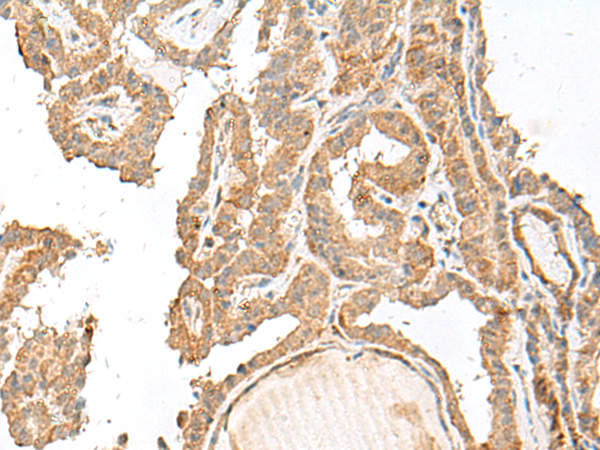

The image is immunohistochemistry of paraffin-embedded Human thyroid cancer tissue using 47569(GART Antibody) at dilution 1/30.(Original magnification: 200)

The image is immunohistochemistry of paraffin-embedded Human cervical cancer tissue using 47569(GART Antibody) at dilution 1/30.(Original magnification: 200)